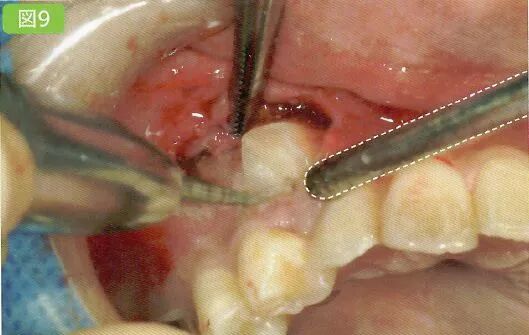

预防水珠飞散

将牙骨、牙冠、牙根置于清晰的视野之下智齿/残根,无论是处于哪一种情况之下,在进行牙骨切削时为了防止牙骨被灼伤,一定要充分注水。注水时在水珠迸溅的地方放上吸唾器,以减少水珠乱飞的情况(图9)在主治医生停下手中动作时利用吸唾器吸引口腔内的水。若是使用涡轮机或者引擎产生的注水量较多,可以换用口腔用吸唾器。

牙冠分割和骨削除的方法根据主治医生的不同也会有所差别,但若是能完成基本出血、注水、削除片等部分的吸引的话,术野的保证也会变得更加容易。

刮匙怎么使用拔牙中吸唾器的使用技巧_https://www.jmylbn.com_新闻资讯_第23张

完成出血点、注水和削除片的吸引,以保证术野的清晰度。